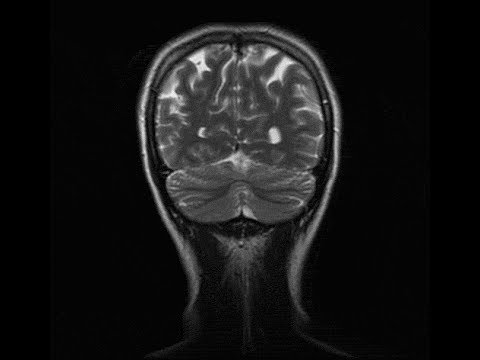

Анатомия мозга: Рентгеновские снимки для презентаций